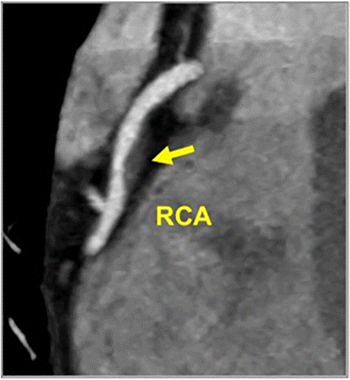

Plaque Analysis and RoadMap Analysis, two artificial intelligence (AI)-enabled assessment products, may enhance clinical evaluation of coronary artery disease (CAD) on cardiac computed tomography angiography (CCTA).

In an update of the original CAD-RADS™ consensus document on coronary artery disease (CAD) imaging and reporting published in 2016, expert panelists incorporated emerging evidence for CAD-RADS 2.0 to recommend new categorization for coronary plaque burden and suggested modifiers to reflect the level of ischemia and high-risk plaque in patients undergoing cardiac computed tomography.